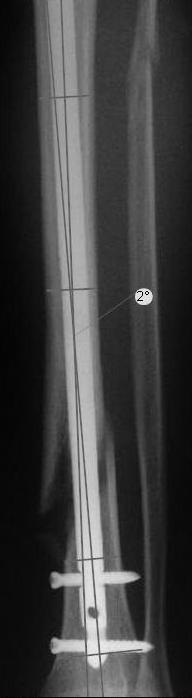

Вы бы стали оперировать или рекомендовали бы своему родственнику оперироваться из-за 2 градусов?

Динамизировать, выкрутив проксимально все винты, на сроке 8 недель ихмо достаточно.

чтобы понять сколько там градусов, необходимо, как минимум, сделать осевые снимки. Я рассуждал по аналогии с протезами коленного сустава, вальгусное или варусное смещение более 3 градусов чревато ранней нестабильности. Почему же для нормального коленного сустава это должно быть хорошо?

Вот именно количественный, т.е. сколько градусов в вальгусе допустимо и при каком диастазе в мм или в % от толщины диафиза.